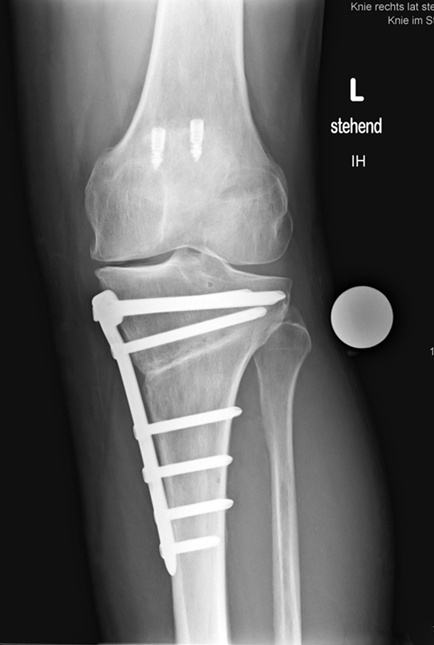

Dr. med. Alexander Strehl: Bei der häufigsten Umstellungsosteotomie am Unterschenkelkopf macht man einen Sägeschnitt am Knochen, klappt diesen gezielt auf und fixiert ihn mit einer winkelstabilen Platte; dies auf Basis dessen, was man vor der Operation bei der Planung gemessen und errechnet hat. Es entsteht ein winkelförmiger Spalt im Knochen, der von selber wieder zuwächst. Je nach Ort und Art der Deformität findet auch der Eingriff statt. Bei einem O-Bein ist dies meistens am Unterschenkelkopf. Es können aber auch Eingriffe am Oberschenkel nötig sein, vor allem beim X-Bein. Bei extremen Deformitäten kann auch eine Doppelosteotomie erforderlich sein, also dass man am Ober- und Unterschenkel korrigieren muss, um wieder eine gerade Achse zu erhalten. Dies muss man im Vorfeld genau analysieren und planen. Während der Operation wird die Beinachse mehrfach mit dem Ausrichtestab überprüft.

Bei Patienten ohne Voroperationen dauert der Eingriff unter zwei Stunden. Bei Voroperationen und vorhandenen Vernarbungen dauert es eventuell länger, da es schwieriger ist, alles zu lösen, um den Knochen aufzuklappen. Eine Doppelosteotomie dauert drei bis vier Stunden.